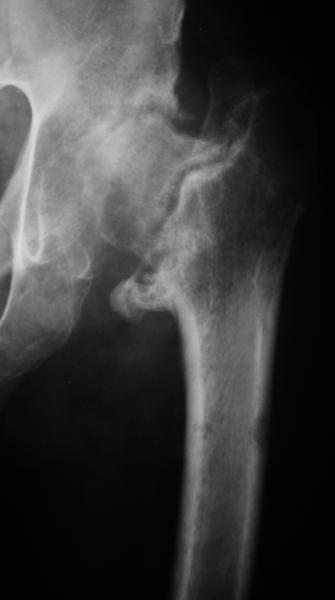

Еще пара фото, ситуация несколько иная, задачи те же, открытое вправление застарелого вывиха в 2002, молодой возраст. Сейчас госпитализирована для эндопротезирования.

--

С уважением,

Агалаков